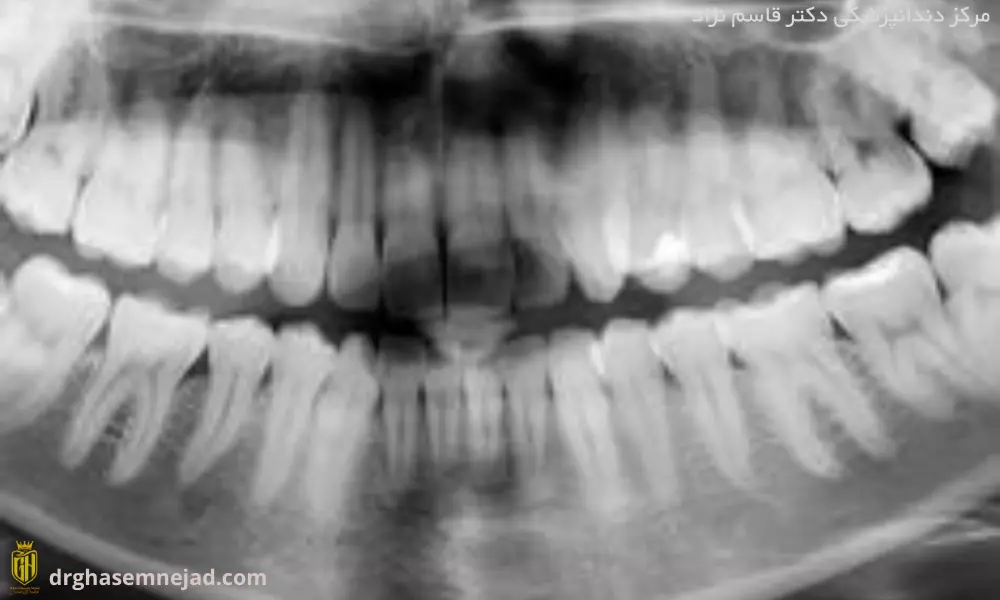

تشخیص وجود حفره یا پوسیدگی در دندان زیر تاج ممکن است دشوار باشد، به خصوص اگر ناحیه آسیب دیده بسیار کوچک باشد. گاهی ممکن است کمی درد را در زیر تاج احساس کنید ولی ممکن است تا زمانی که پوسیدگی در مراحل پایانی قرار نگیرد دردی رخ ندهد. با معاینات منظم دندانپزشکی، دندانپزشک شما میتواند از دندانهای شما با اشعه ایکس عکسبرداری کند تا مشخص شود که آیا آسیب یا پوسیدگی زیر تاج شما وجود دارد یا خیر.

بنابراین، مادران باردار باید برای مشاوره و مراقبت از بهداشت دهان و دندان خود زودتر اقدام کنند. همچنین قبل از انجام عکس OPG به دندانپزشک معالج خود اطلاع دهید که باردار هستید. زیرا در مواردی که ممکن است نیاز به عکس برداری با اشعه ایکس باشد، دندانپزشک میزان اشعه مناسب برای شما و بارداری شما را در نظر می گیرد. همچنین باید در هنگام اشعه ایکس با استفاده از تجهیزات محافظ سرب، از خود محافظت کنید و مطمئن شوید که فقط از داروهایی استفاده می کنید که برای زنان باردار بی خطر است.

عکس OPG جهت تشخیص پوسیدگیپوسیدگی دندان کودکان

پیش از انجام ارتودنسی میبایست از سلامت دهان و دندان خود اطمینان حاصل کنید، به طوری که پس از انجام ارتودنسی دچار پوسیدگی دندان نشوید. در این خصوص میبایست از دندانپزشک خود بخواهید تا دندانهای شما را معاینه کند و با عکس OPG تمام دندانهای شما را چک کند تا اگر دچار پوسیدگی دندان و یا سایر بیماریهای دندان و لثه هستید درمان کنید. اگر قبل از ارتودنسی از سلامت کامل دهان و دندان خود اطمینان حاصل کنید، پس از آن به مشکل بر نخواهید خورد.